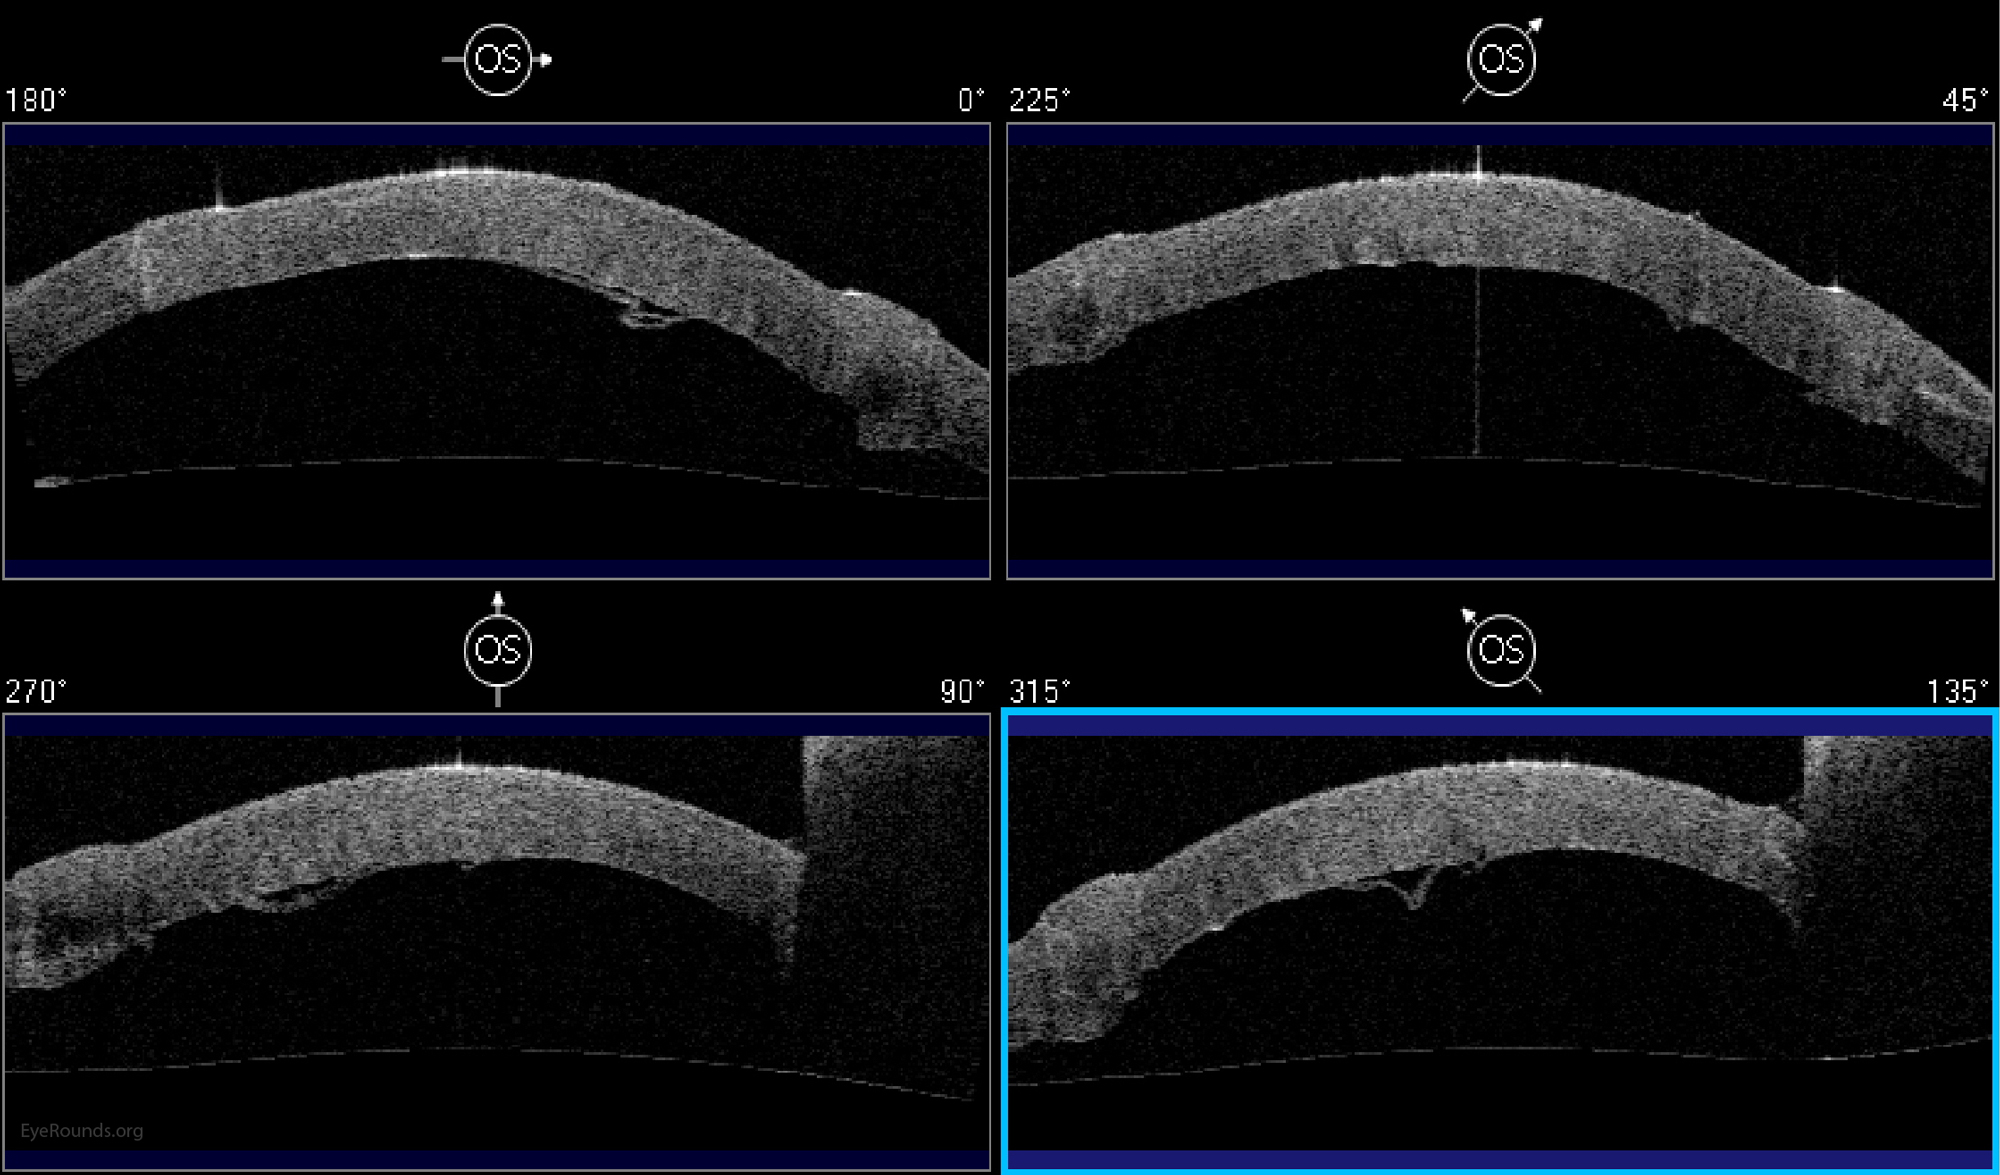

DALK is a partial-thickness cornea transplant procedure that involves selective transplantation of the corneal stroma, leaving the native Descemet membrane and endothelium in place. A trephine of an appropriate diameter is used to make a partial-thickness incision into the patient's cornea, followed by pneumodissection or manual dissection of the anterior stroma. This is followed by placement of a graft prepared from a full-thickness punch in which the donor endothelium-Descemet membrane complex has been removed. The intention is to preserve the patient's Descemet membrane and endothelium. Similar to PK, the graft is secured with interrupted and/or running sutures (Figure 5) and these are then selectively removed post-operatively (Figure 6).

The surgery is more complex and difficult to perform than PK. If the Descemet membrane is perforated intraoperatively, the surgeon must convert to a PK. The "big bubble" technique makes dissection more consistent and is the preferred technique at our institution (12).